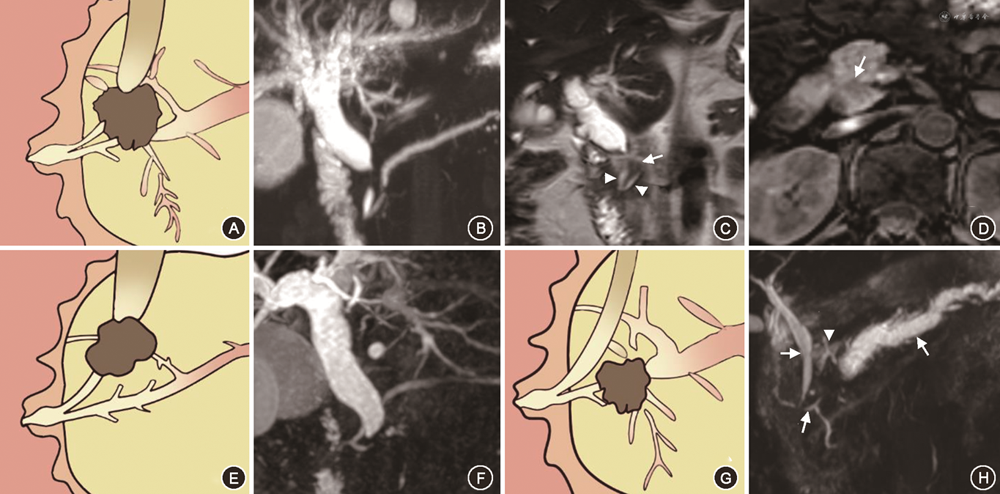

在对有意义单因素指标的分析中,笔者将PAC的MRI征象进行总结,最后归纳为十二指肠乳头结节型、胰腺肿块型、胆总管壁增厚型、壶腹部肿块型及胆总管腔内结节型5种表现类型。十二指肠乳头结节型MRI征象为位于十二指肠腔内的病灶,多为等信号,在十二指肠乳头形成突入腔内的结节,MRCP上胆总管及胰管扩张呈双管征,胰胆管角度较小,双管征走行呈平行或聚拢(图1)。胰腺肿块型MRI征象为胰腺内低信号肿块,MRCP上胆总管及胰管单独或同时狭窄截断可分别出现双管征、三管征、四管征,截断胰管周围可见扩张侧支,肿块引起胰胆管角度增大,管征呈分离走行(图2)。胆总管壁增厚型MRI征象为胆总管远段管壁增厚,近段胆管扩张,MRCP上胰管较少扩张,近段扩张胆管、梗阻下方远段胆总管与胰管呈三管征(图3)。壶腹部肿块型在MRI图像上表现为壶腹部跨壁生长的肿块,可与胰腺、十二指肠肠壁分界不清,但较少使十二指肠乳头表现为结节型,MRCP管征多为双管征(图4)。胆总管腔内结节型在MRCP图像上远端胆总管内见结节样充盈缺损伴胆道梗阻,远段胆总管、近段扩张胆总管及胰管呈三管征(图5)。

Fisher精确概率法结果显示,IPAC与PPAC在MRI影像5分型的差异具有统计学意义(P<0.001)(表4)。经调整检验水准后的 Bonferroni 法两两比较结果显示,十二指肠乳头结节型与胰腺肿块型、胆总管壁增厚型及壶腹部肿块型的差异均具有统计学意义(均P<0.005)。IPAC多表现为十二指肠乳头结节型(15/21,71.4%)(图1),PPAC更多表现为胰腺肿块型(18/38,47.4%)、胆总管壁增厚型(9/38,23.7%)或壶腹部肿块型(9/38,23.7%)(图2, 3, 4),IPAC(2/21,9.5%)与PPAC(0,0)均较少表现为胆总管腔内结节型(图5)。

PPAC更多表现为胰腺肿块型、胆总管壁增厚型及壶腹部肿块型。在本研究中,PAC最常见的分型为胰腺肿块型,这与Williams等[2]的报道结果一致,PPAC在MRI图像上可出现类似于胰腺癌的影像征象。在本研究中,共有10例PAC表现为胆总管壁增厚型,其中9例为PPAC。Williams等[2]在PAC组织学亚型的病理分析中发现86%的远端胆管癌为胰胆管型;而方三高等[10]报道PAC中胰胆管型肿瘤的浸润性组织学特征高于肠型;而本研究数据显示,在MRI图像上PPAC中表现为浸润型的比例(23.7%)高于IPAC(4.8%),笔者考虑表现为胆总管壁增厚型的PPAC可能多起源于远端胆总管,并由于其浸润性的生长方式,从而在MRI图像上出现与远端胆管癌“围管性”浸润生长相似的形态特征。本研究结果也与文献相似。